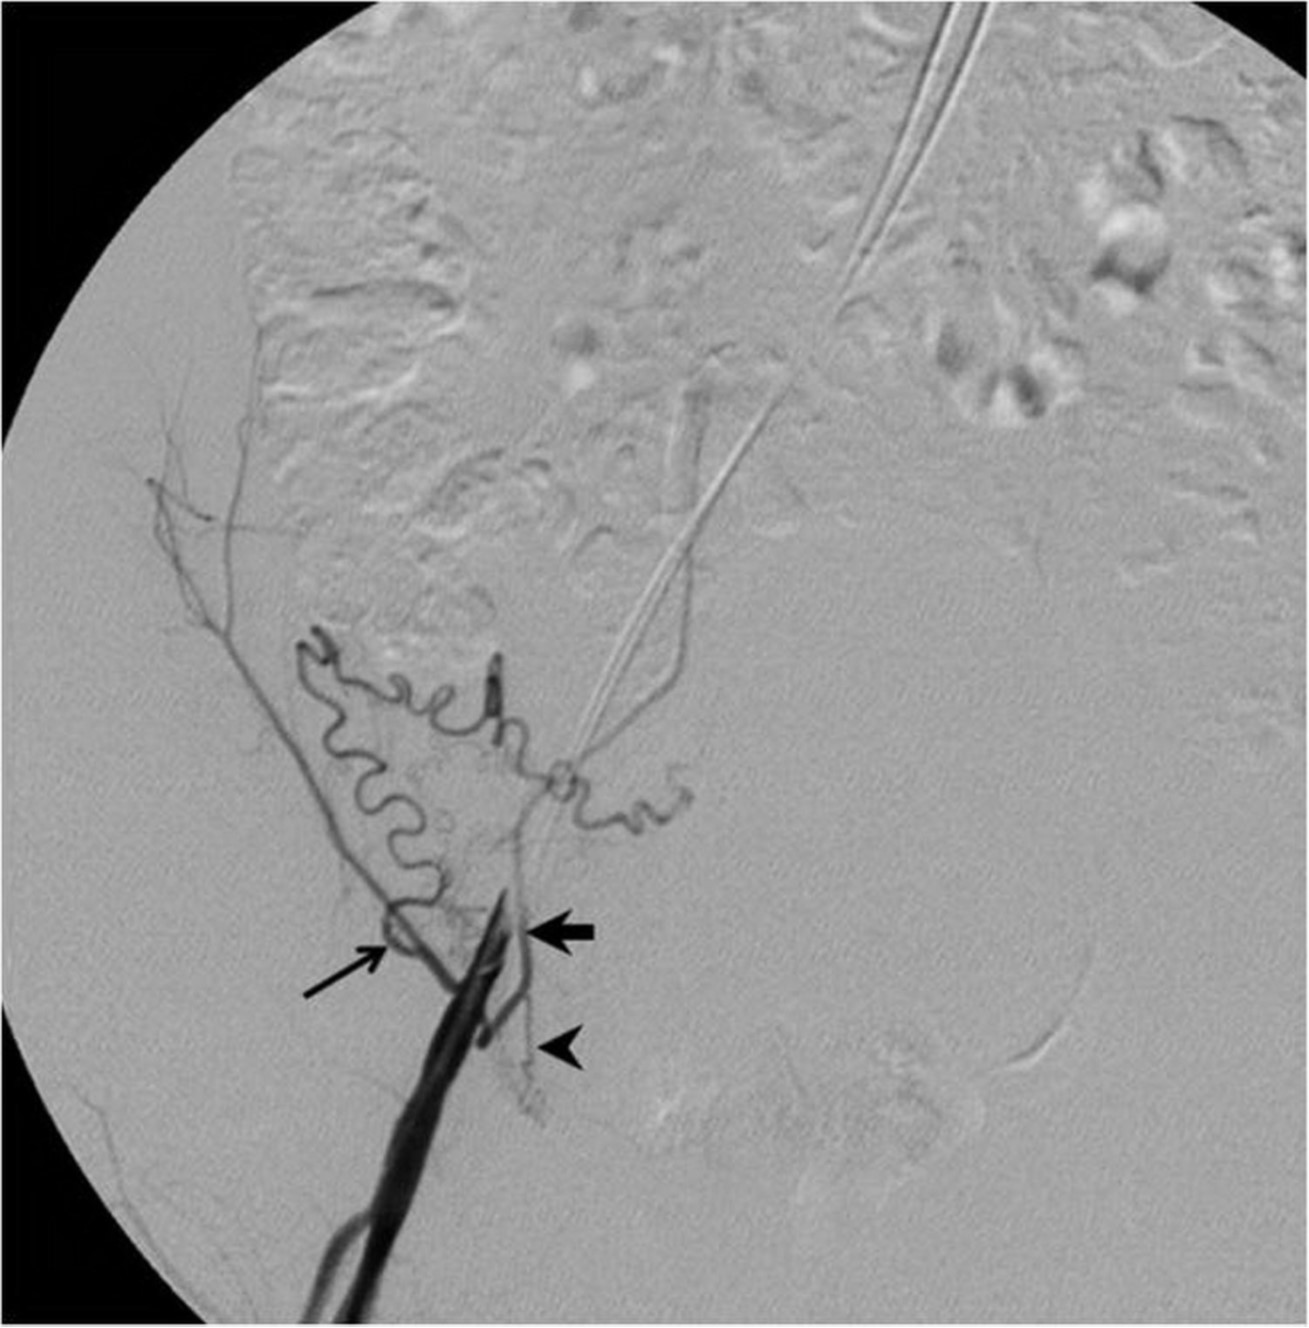

Fig. 1.

Fig. 1. T2-weighted sagittal MR image shows multiple submucosal and intramural uterine myomas, with the largest one measuring 6.1 x 4.2 x 5.9 cm.

자기공명영상에서 조영증강이 되는 다발성 자궁근종이 있었고, 가장 큰 것의 크기는 6.1 x 4.2 x 5.9cm로 측정되었다(Fig. 1).